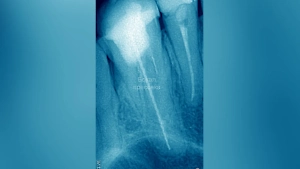

Головные боли могут возникать по ряду причин, однако порой они могут быть обусловлены проблемами с зубами. Как пояснила в беседе с Life.ru ортодонт, гнатолог и руководитель клиники «ОМдоктор» Оксана Московец, хронические головные боли достаточно часто бывают вызваны отсутствием нескольких зубов.

Как известно, наша нижняя челюсть это единственная кость черепа, которая соединена с ним не через костные структуры, а через мышцы и связки. Грубо говоря, нижнюю челюсть поддерживают в пространстве в основном жевательные мышцы. Для адекватной работы этих мышц очень важно чтобы при жевательном давлении нагрузка была равномерно распределена по всем зубам. Когда по каким-либо причинам теряем зубы, особенно боковые, нашей зубочелюстной системе приходится перераспределять силы для компенсации потерянного зуба.

Кроме того, потеря зубов нередко ведёт к дисфункции височно-нижнечелюстного сустава. При уменьшении высоты прикуса суставные головки оказываются под давлением, что вызывает боли, шум в ушах и затруднения при открывании рта.